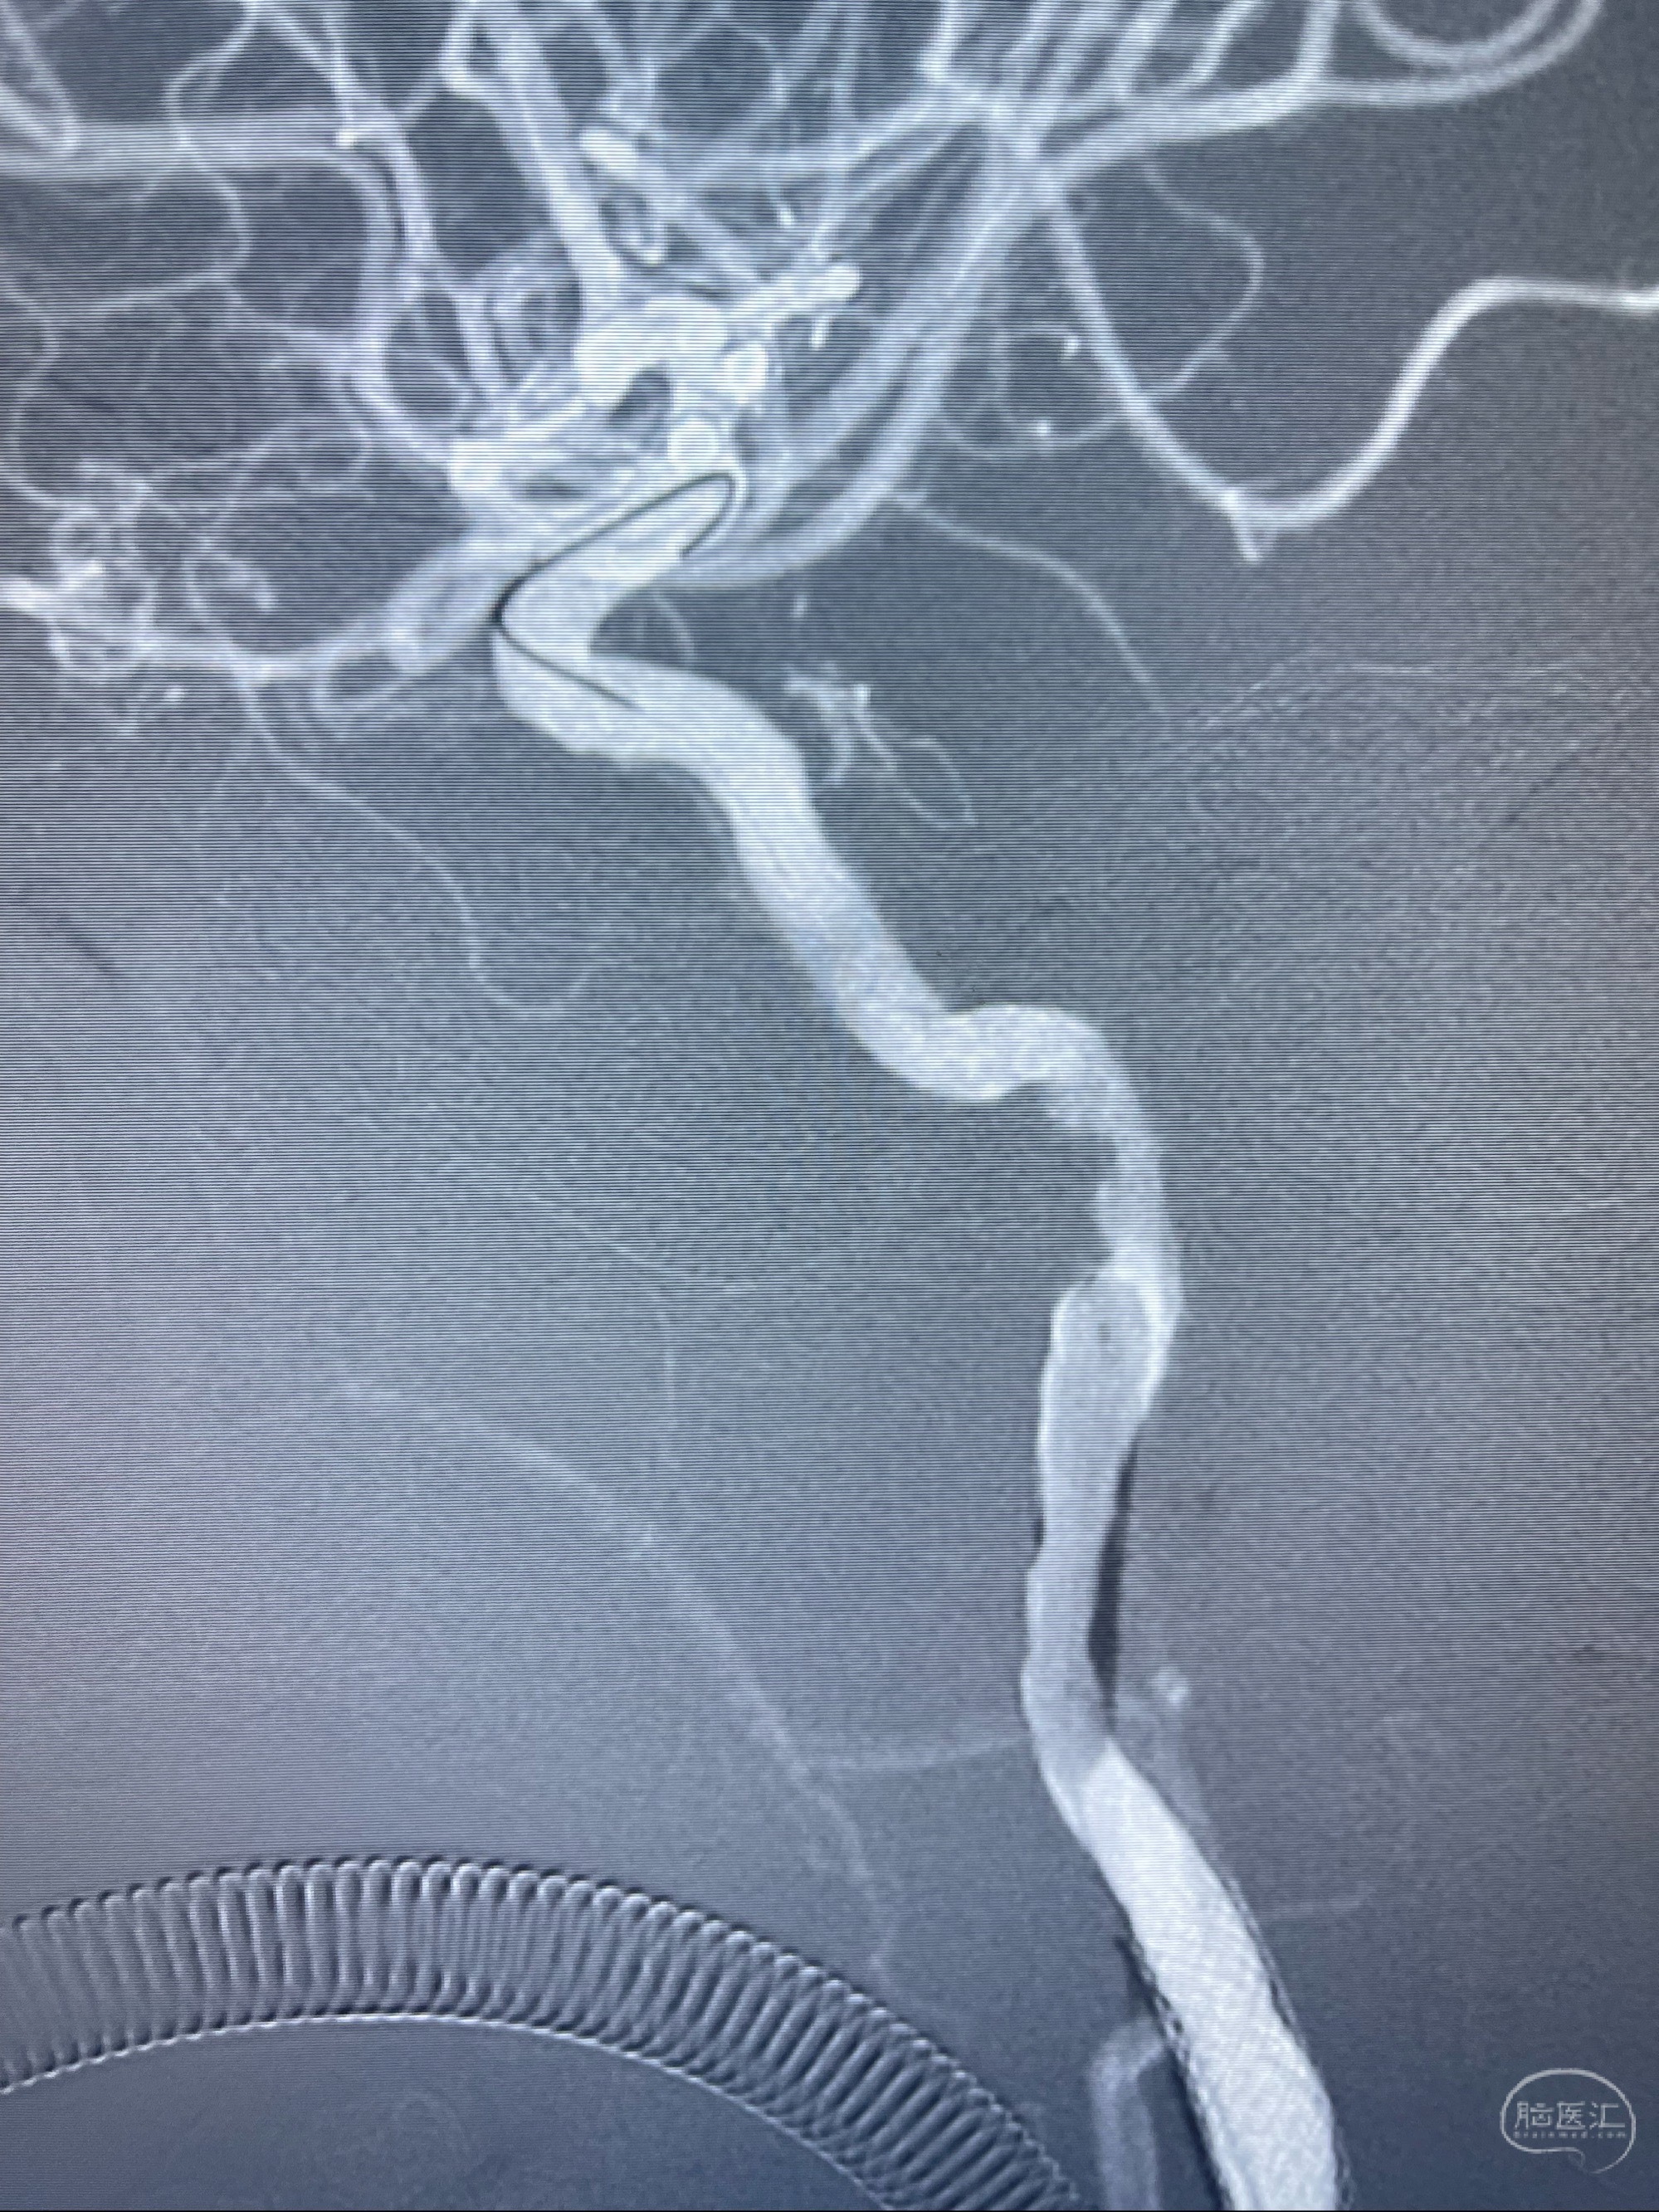

即刻造影显示狭窄扩张佳

重新行“路径图”,支架导管在微导丝引导下超选择性插入至右侧颈内动脉眼段,4.5-50mmLeo支架释放,远心端位于海绵窦段,近心端位于岩骨段狭窄段以近

即刻造影显示支架贴壁佳

支架完全打开,近心端位于原颈动脉支架远心端内